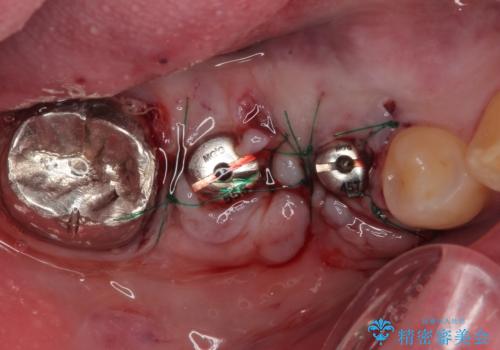

抜歯即時埋入部と後方の欠損部は、即日荷重(インプラント埋入と同時に仮歯を装着すること)が可能な安定値が得られましたが、長い期間欠損した状態で過ごすと、欠損部に舌を押し当てる癖が発現してしまい、舌からの側方圧でインプラントが脱離するリスクが著しく高まってしまうため、即日荷重は行いませんでした。

おかげでインプラントは無事に生着し、僅か4ヶ月で治療を終えることができました。